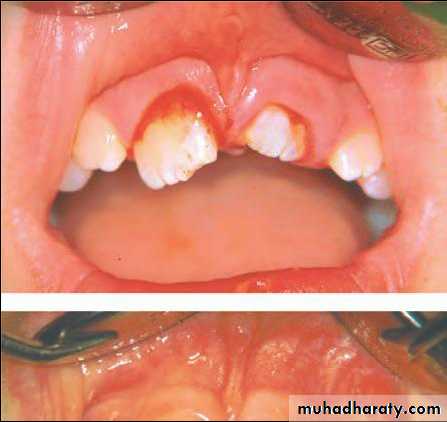

Crown-root fracture

Incisors with crown-root fractures